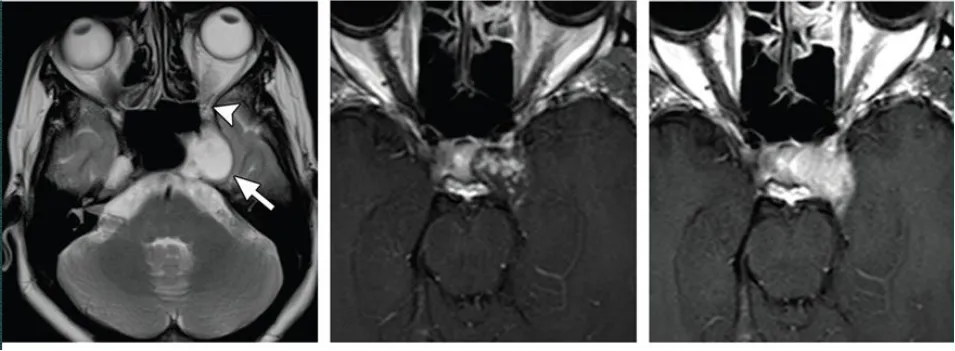

圖:海綿竇腦膜瘤合并左側(cè)頸內(nèi)動脈狹窄,手術(shù)難度大

海綿狀神經(jīng)鞘瘤,瘤內(nèi)間囊變,實性部分明顯強化。

圖:海綿狀神經(jīng)鞘瘤,瘤內(nèi)間囊變,實性部分明顯強化。

海綿竇血管瘤,T2高信號,累及左側(cè)Meckel腔

圖:海綿竇血管瘤,T2高信號,累及左側(cè)Meckel腔

軟骨肉瘤,巖尖膨脹性骨質(zhì)破壞,累及左側(cè)海綿竇后部

圖:軟骨肉瘤,巖尖膨脹性骨質(zhì)破壞,累及左側(cè)海綿竇后部